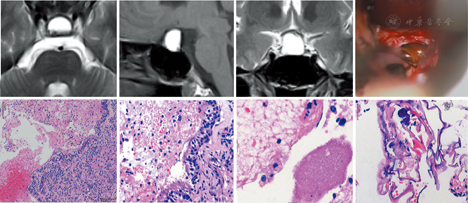

患者女,21岁。以"头痛20余天,突发左眼视野缺损10余天"主诉入院。当地眼科检查提示:左眼视力为0.04,矫正视力为0.15,颞侧及中心暗点;右眼视力为0.15,矫正视力为1.0,上方视野弓形缺损。头颅CT提示鞍区占位。体格检查:双眼视力粗试下降,左眼颞侧视野缺损,右眼视野粗试正常;神经系统未见阳性体征。既往身体健康,月经周期规则。MRI显示:垂体窝扩大,鞍内及鞍上可见囊性占位性病变,大小约18.2 mm×17.4 mm×17.7 mm,边界清楚,T1WI及T2WI均呈高信号,T2WI显示其内可见液-液平面(图1A,图1B,图1C);正常垂体未见显示,垂体柄及视交叉受压。考虑垂体腺瘤卒中的可能性较大。血清激素检验(晨血6:00):促肾上腺皮质激素<1.6 pg/ml(正常范围为4.7~48.8 pg/ml),皮质醇为0.80 μg/dl(正常范围为4.3~22.4 μg/dl),余激素均在正常范围。入院第3天在全身麻醉下行经鼻蝶入路鞍区病变切除术。术中细针穿刺鞍底硬脑膜,抽出暗红色囊液1.5 ml;切开鞍底脑膜,鞍内前部流出少许褐黄色囊液(图1D);正常垂体组织呈粉红色,切开鞍底正常垂体组织,于鞍内后部流出暗红色囊液。清除鞍内异常组织和出血,保留变黄色的垂体组织。术后患者头痛缓解,视力、视野较术前明显改善,术后4 d出院。临床诊断:无功能性垂体大腺瘤伴全瘤型卒中。组织病理学检查(图1E,图1F,图1G,图1H):部分区域呈囊壁样结构,囊内壁衬附假复层柱状纤毛上皮,囊壁和垂体组织内存在慢性炎性反应,囊内含血块、坏死物质及少量炎性渗出。病理学诊断:RCC出血,囊肿壁破裂。

RCC因内容物成分的不同,MRI可表现T1和T2像呈高信号、等信号或低信号,甚至混杂信号或沉积分层等现象[1]。当RCC出血时,血肿与内容物混杂,影像学表现会发生变化。有学者发现,因鞍膈不易发生形变,RCC在向鞍上扩展时,囊肿分隔垂体后叶漏斗与结节部,在接触鞍膈处形成一凹面,而垂体后叶在囊肿与鞍膈之间会形成一凸向囊肿的平面,两平面在影像学上形成"鞍膈后缘"现象,该现象的存在被认为是RCC的特征性表现,当RCC出血时,这一影像学特点会消失[9]。多数作者认为,RCC出血并无特征性影像学表现,但T1与T2加权像上均表现高信号者多见[3,5,10,11]。本例在T1、T2加权像上主要呈高信号,与报道基本一致。但本例患者同时伴有一很低的液-液平面(即液-液平面以下的部分所占的比例很小),以及在囊内所见的低信号结节和似囊内分隔的不连续线样低信号,影像学表现很独特,这一少见现象说明RCC出血的影像学表现复杂多样。

结合本例术中所见及组织病理学,分析其影像学特点的形成机制可能为:RCC由于增大和炎性反应等原因而致囊壁破裂,囊周的垂体被撕裂出血,流入囊内,囊液与出血以及液化的血肿间分层,形成液-液平面;低信号的"结节"比液平面下的囊液信号更低,推断其应是RCC原来的囊内结节;囊内不连续线样低信号似呈隔膜状,可能是原来囊内黏液的蛋白质成分被排挤和凝聚而成,也可能是囊壁纤维化导致囊壁增厚所形成的征象。

本例的MRI表现是以高信号为主的纯囊性病变,囊内信号不均,垂体显示不明显,与全瘤型垂体卒中以及垂体慢性血肿均极为相似[17,18]。但本例也有特别之处:一是比液平面以下囊液信号更低的结节信号,其边界清晰,提示病变可能为RCC;二是病变在MRI上的超低液平,提示该病灶发生出血前为囊性病变,尽管可以是囊性垂体腺瘤,也可能是囊性而缺少明显结节的RCC。